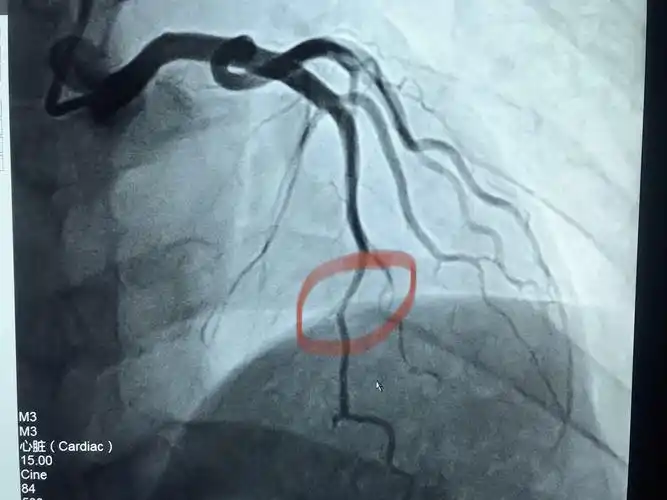

冠状动脉狭窄的血管造影

冠脉造影提示:左冠状动脉的前降支也有重度狭窄